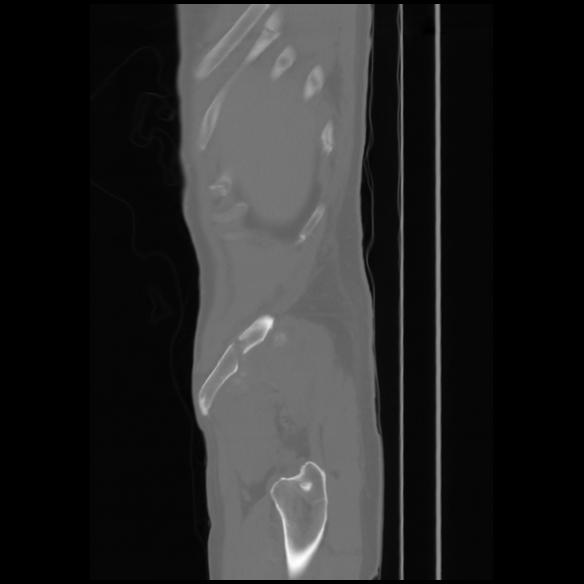

7 CUERPO,CE,Sagittal,3.000,CUERPO,Sagittal,